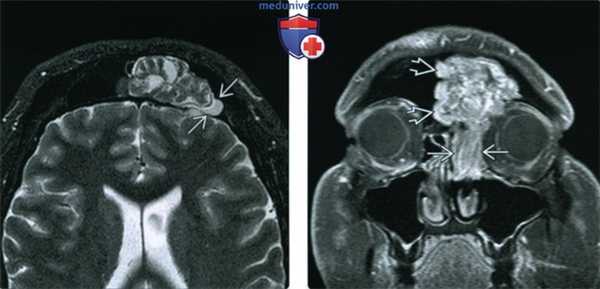

(Слева) При аксиальной МРТ STIR визуализируется инвертированная папиллома с типичной архитектурой, напоминающая кору мозга. «Запертый» секрет снаружи гипоинтенсивен по сравнению с папилломой. Папиллома редко возникает в лобной пазухе.

(Справа) При корональной МРТ Т1 С+ FS визуализируется инвертированная папиллома в решетчатых пазухах и в лобной пазухе. «Запертый» секрет вдоль края опухоли в лобной пазухе содержит белок (укорочение Т1).